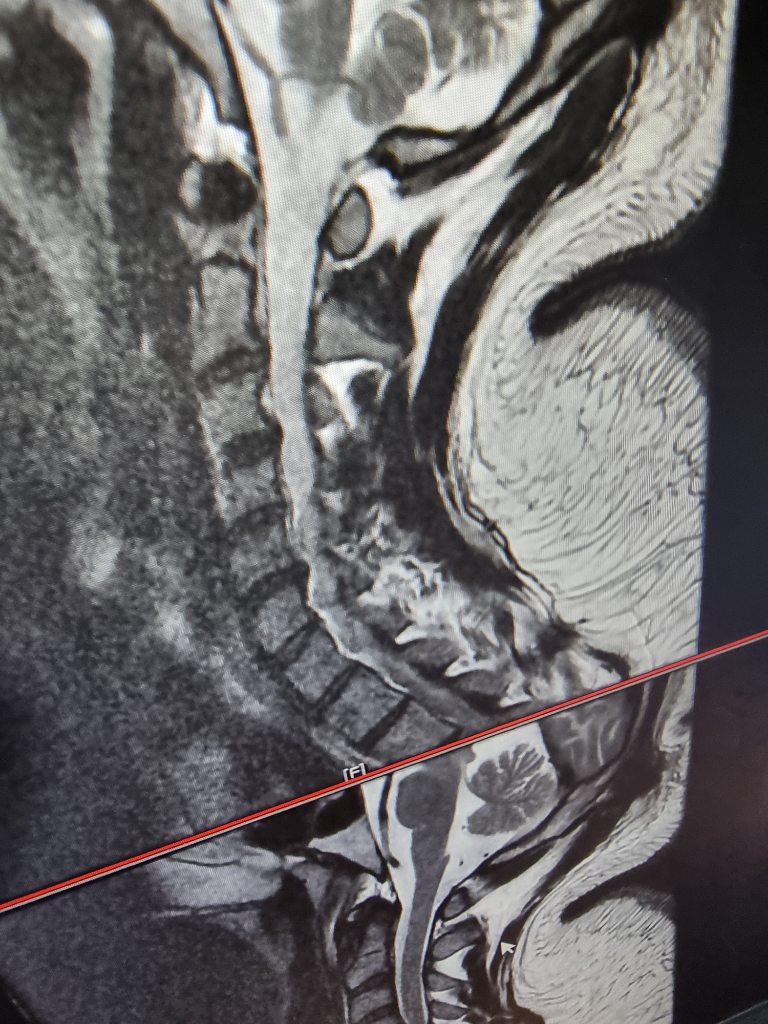

경추 후종인대 골화증 ct mri 사진좀 봐주세요...

척수병증이 MRI에서 보일려면 척수에 병변이 있어야 합니다, 그러니까 색이 변해야 하는거죠

현재는 그런 양상은 보이지 않고 표시한 부분에서 압박하는 양상만 보입니다

신경외과 교수님 말씀에 동의합니다